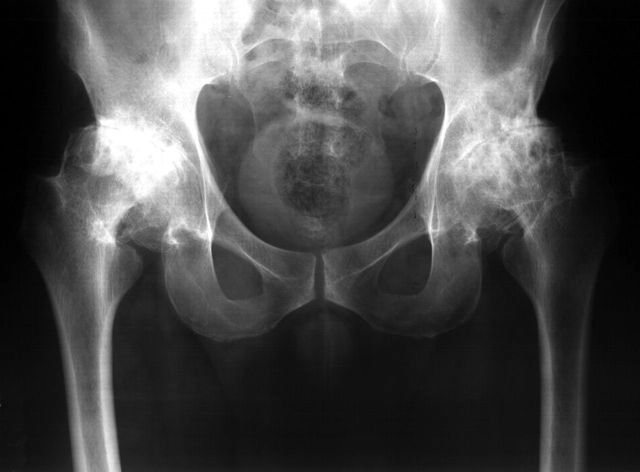

Боль в тазобедренном суставе, как правило, свидетельствует о появлении патологического процесса в анатомических структурах самого сустава либо прилегающих к нему тканей и органов. Наиболее часто болевые ощущения вызывает механическое повреждение, воспалительный процесс, инфекционное либо эндокринное заболевание. Не исключены и другие факторы, которые могут спровоцировать появление этого симптома. Рассмотрим, почему болит тазобедренный сустав и как справиться с этой проблемой.

- рентген тазобедреннного сустава, позволяющий обнаружить или исключить травматическое повреждение, выявить костные дефекты, разрастания и другие патологии;